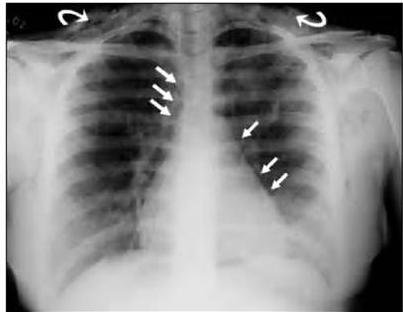

Cardiopatia congênita (provavelmente tetralogia Fallot)

Vamos analisar: temos desnutrição, baqueteamento digital, poliglobulia maciça, sopro sistólico e arco aórtico á direita. São sinais patognomônicos para hipoxia cronica causada por algum defeito cardíaco. Cardiopatias congênitas são anomalias do aparelho circulatório presentes desde o nascimento, sendo divididas em cianóticas e acianóticas. A Tetralogia de Fallot é a cardiopatia cianótica mais comum, caracterizada por comunicação interventricular, estenose subpulmonar, origem biventricular da valva aórtica e hipertrofia ventricular direita. O diagnóstico costuma ser realizado no primeiro ano de vida devido às manifestações clínicas precoces, na maioria dos casos. Contudo, em alguns casos, a associação de outras malformações cardíacas e falhas no sistema de saúde podem contribuir para realização de diagnósticos tardios, aumentando a probabilidade de prognósticos desfavoráveis.